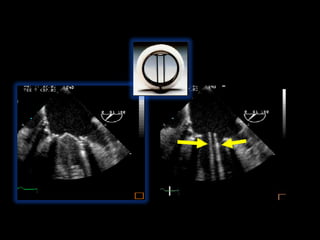

1.Reverberations

1.Beam Width Artifacts

Reverberation Artifact

Side Lobe Artifact

Ultrasound Assumption Violations Anotherway to think about these Axial Direction Artifacts located below the real Structure Lateral Direction Artifacts located to the side of the real Structure 1.Reverberations 2.Mirror Image Artifacts 3.Acoustical shadowing or enhancement 1.Beam Width Artifacts 2.Side Lobe Artifacts 3.Refraction Artifacts